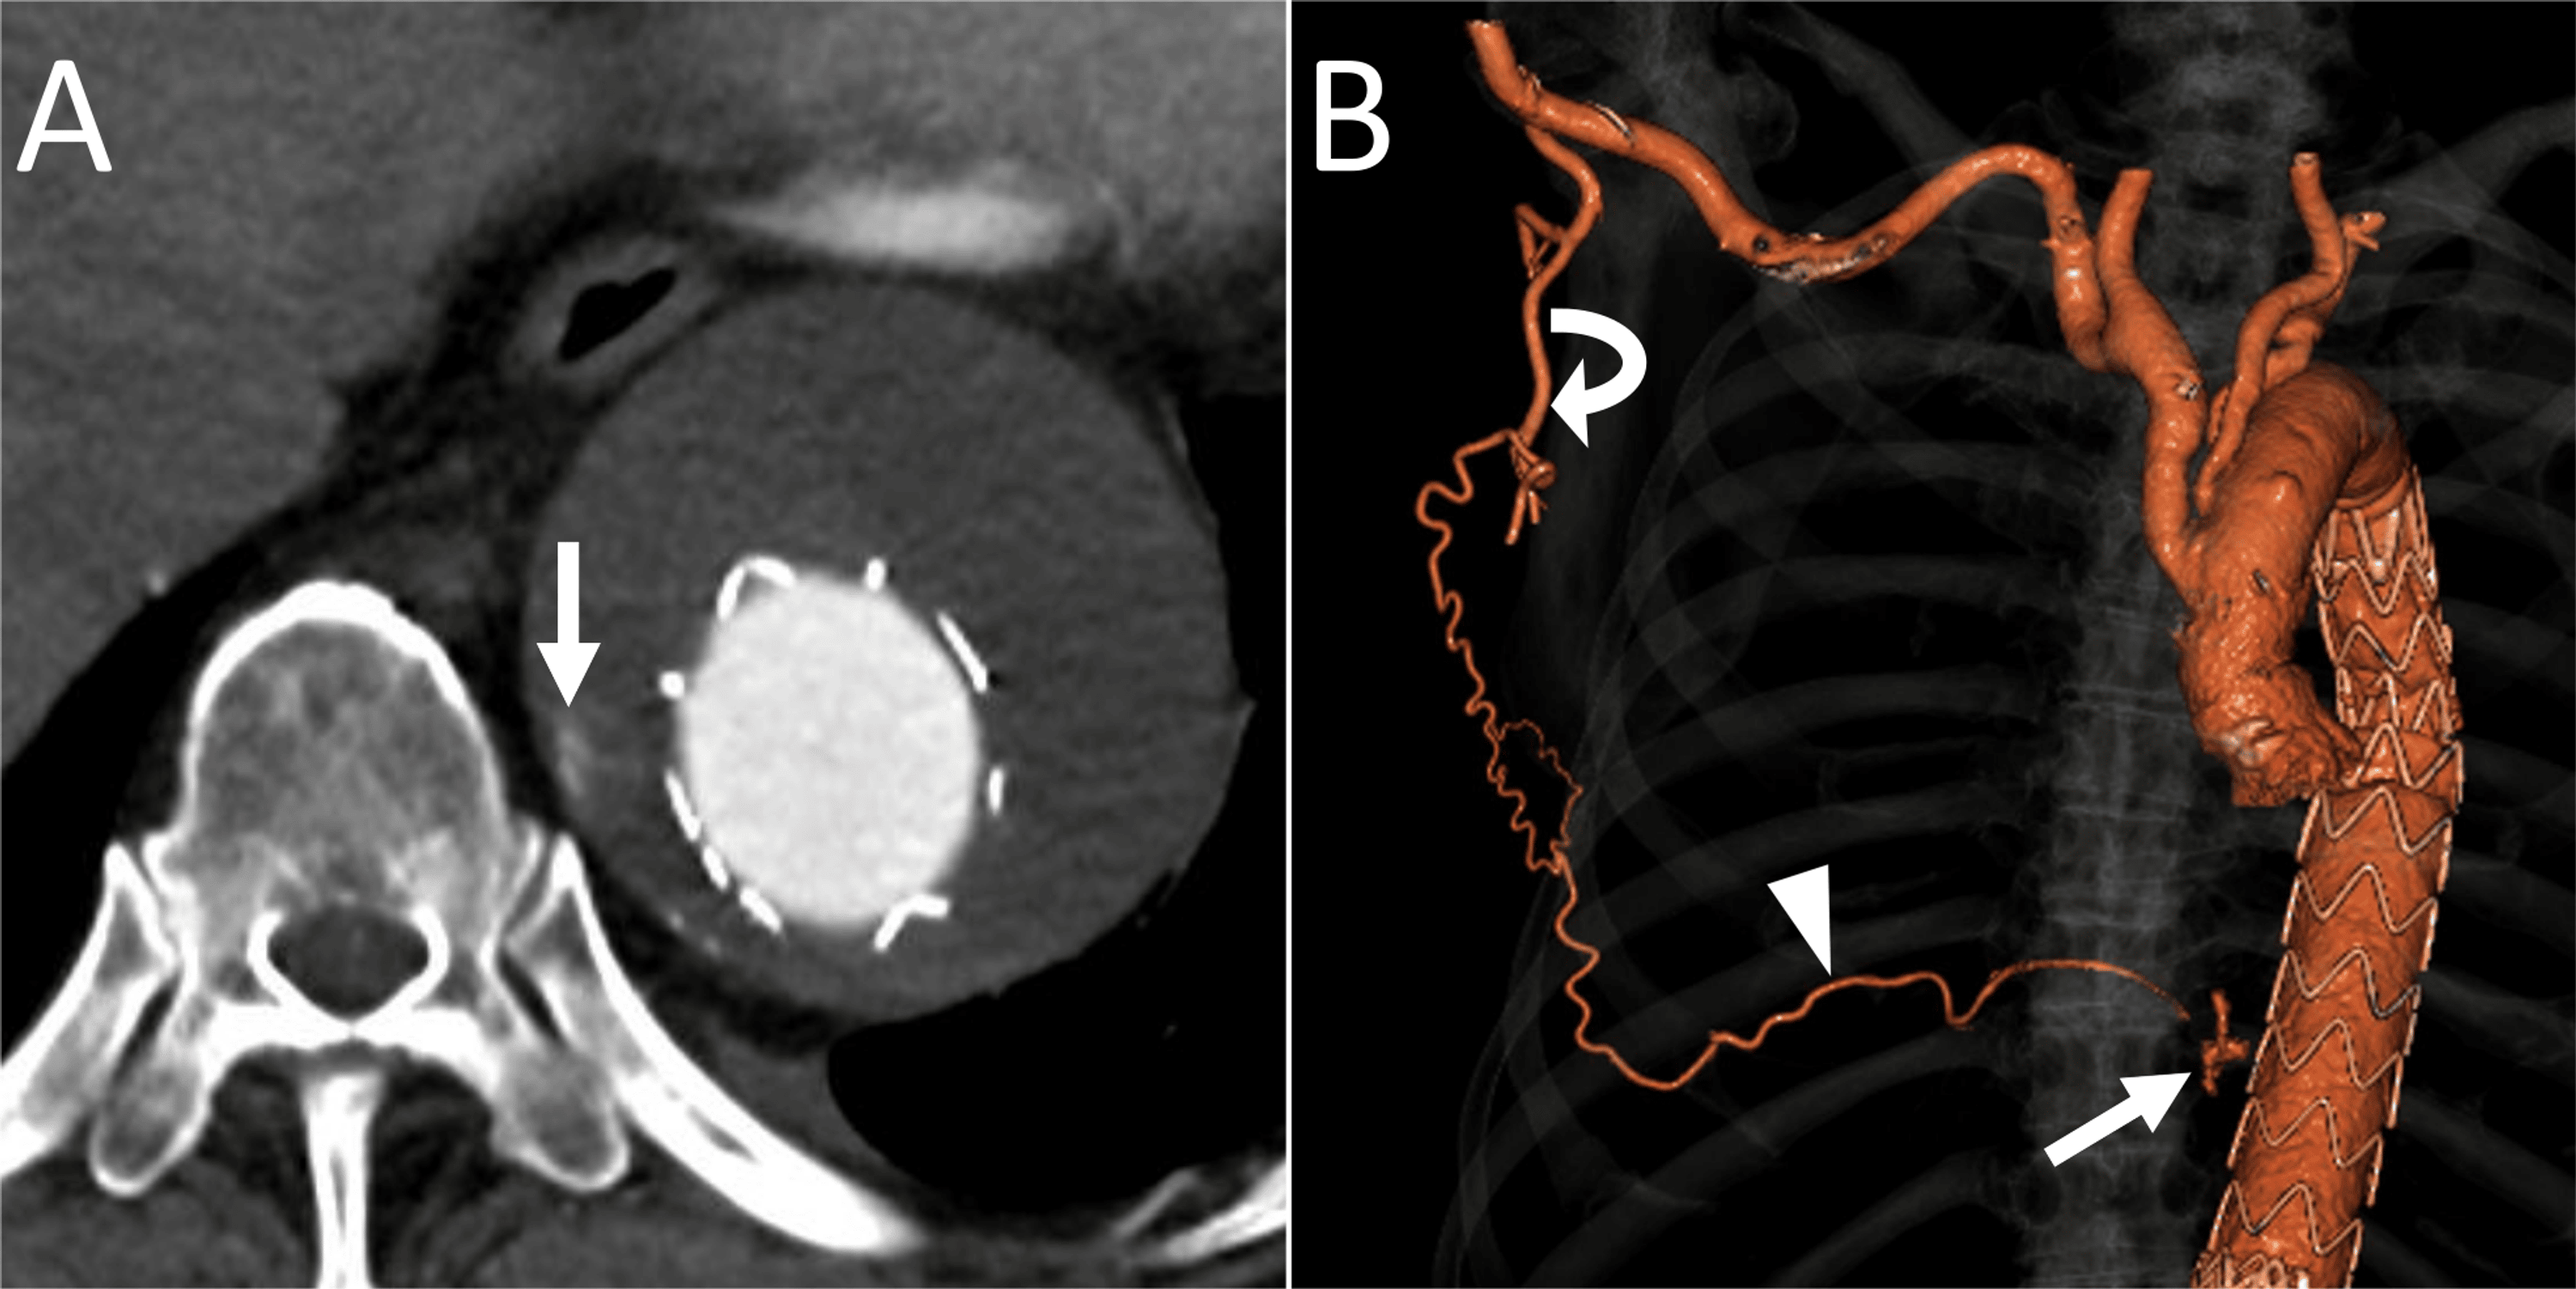

Transarterial embolization of a type IIa endoleak via the right lumbar

Type II endoleak treated with translumbar embolization. (a) CTA Coil Embolization Of Type 2 Endoleak Embolization procedures for type ii endoleak after endovascular abdominal aortic repair in 315 patients resulted in freedom from aneurysm enlargement (>5. We report outcomes of translumbar embolization (tle) of t2es following evar. We conducted a retrospective chart review of patients with t2e after evar treated with tle from 2011 to 2018 at a single academic institution. 13,14 different embolic agents,. Coil Embolization Of Type 2 Endoleak.

Transarterial Embolization of Type 2 Endoleak Post Thoracic Coil Embolization Of Type 2 Endoleak We conducted a retrospective chart review of patients with t2e after evar treated with tle from 2011 to 2018 at a single academic institution. We report outcomes of translumbar embolization (tle) of t2es following evar. 13,14 different embolic agents, coils, microcoils, glue, liquids, and plugs can be used alone or in combination. Persistent type 2 endoleaks, defined as endoleaks lasting. Coil Embolization Of Type 2 Endoleak.